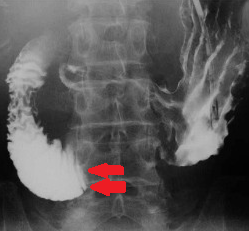

Red arrows — transition point. Multiple air-fluid levels (Courtesy Dr. V. Penopoulos)